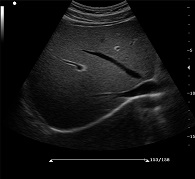

C7便攜式彩超產(chǎn)品說(shuō)明:

? ? ? ?C7為深圳安盛生物醫(yī)療技術(shù)有限公司新一代便攜式彩超產(chǎn)品,采用了先進(jìn)的PC平臺(tái),擁有強(qiáng)大的處理能力,優(yōu)異的圖像性能,集小巧輕便、全面的功能與輕巧流暢、特有的U型設(shè)計(jì)與一身,提供大眾新選擇。

先進(jìn)的成像技術(shù):

? ?● PHI脈沖反相組織諧波成像+頻率復(fù)合技術(shù)

? ? ? ?保證良好穿透力的同時(shí)獲得更加細(xì)膩的二維圖像

? ?● 空間復(fù)合成像技術(shù)

? ? ? ?通過(guò)多個(gè)角度圖像復(fù)合減弱單一圖像偽像,提高信噪比

? ?● 斑點(diǎn)噪聲抑制技術(shù)

? ? ? ?消除二維圖像斑點(diǎn)噪聲,顯著提高圖像信噪比

? ?● 多種成像模式

? ? ? ?B、C、PW、CW、BCD三功、大角度偏轉(zhuǎn)成像、實(shí)時(shí)寬景成像、梯形成像(僅支持線陣)、解剖M型、彩色M型成像、組織多普勒成像、3D/4D成像